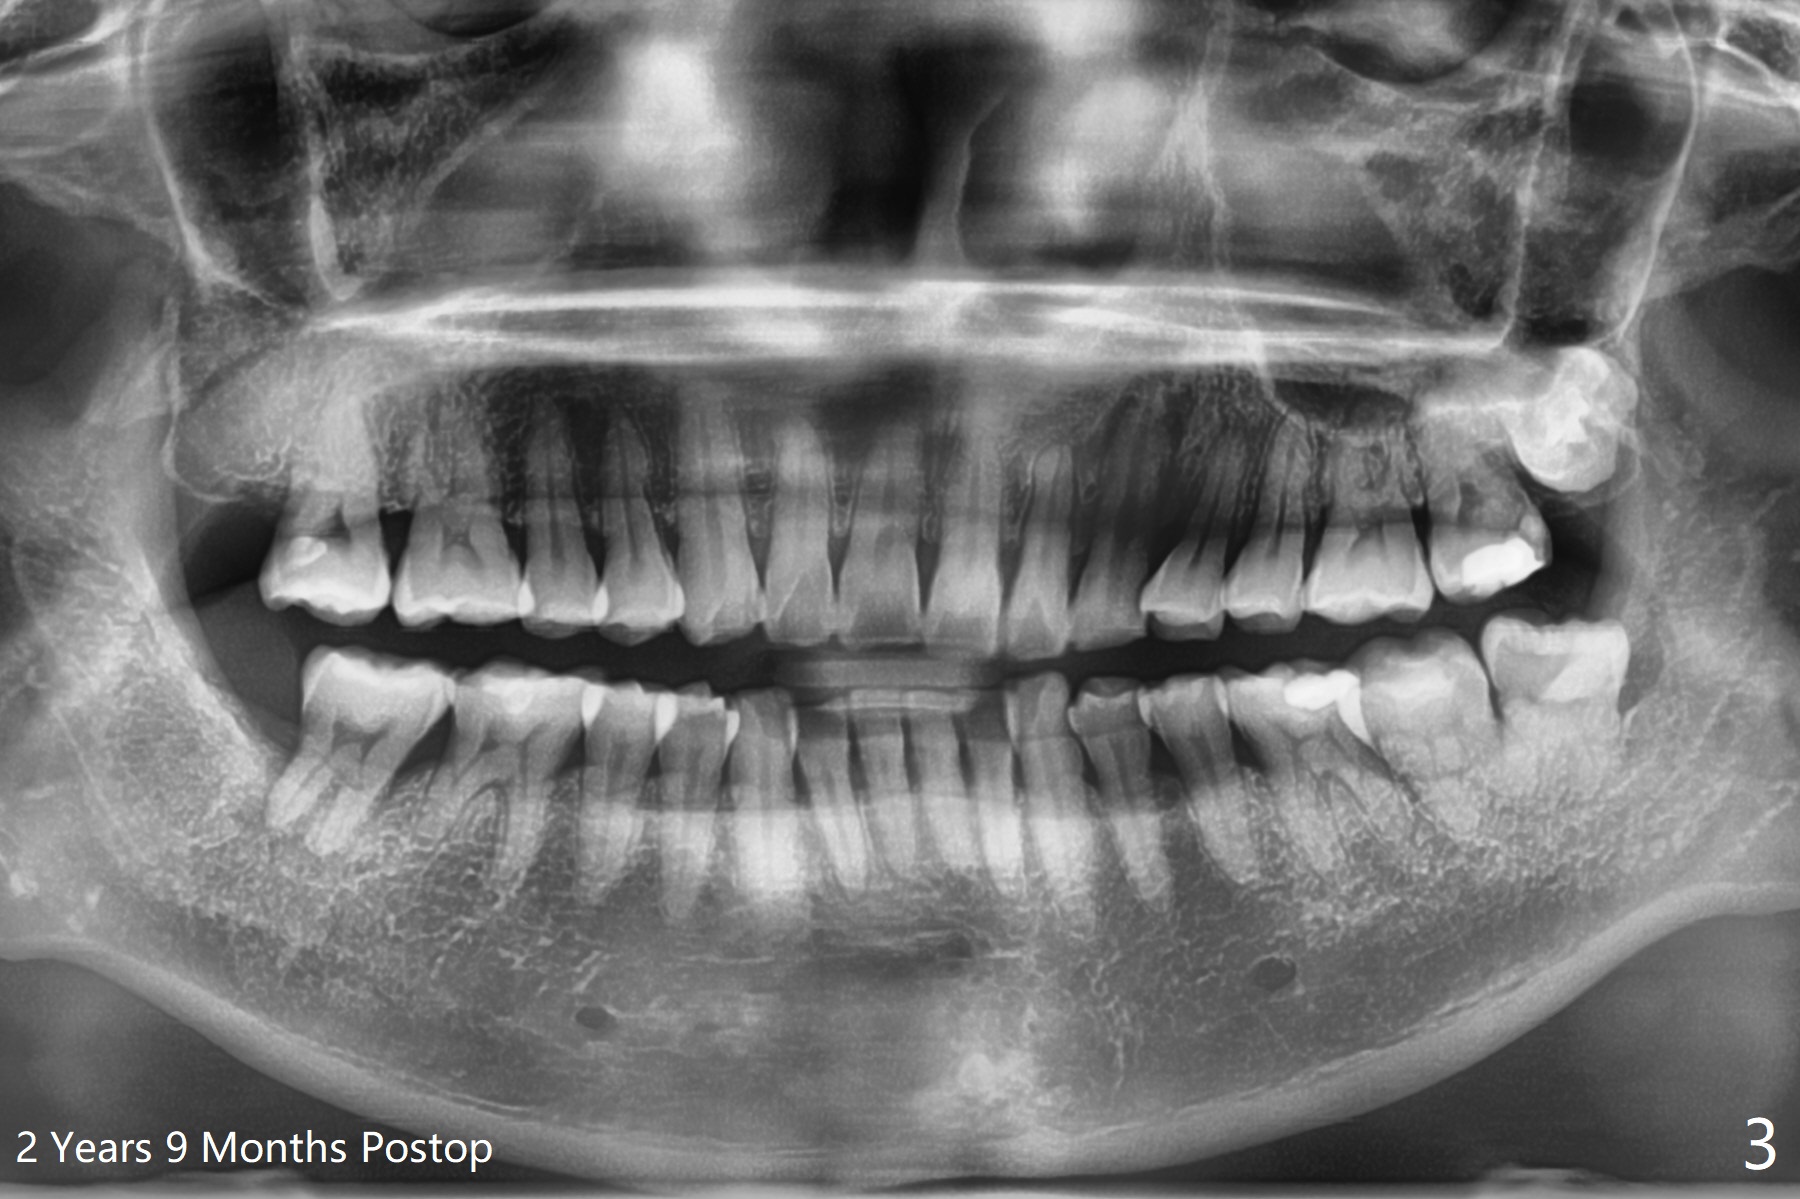

A 44-year-old woman agrees to have #32 extraction to alleviate #31 distal bone loss (Fig.1).  IANB, hockey-stick incision made, reflected mucoperiosteal flap, buccodistal trough, sectioned for multiple times, straight elevator/forceps removal, curette to remove tooth bud sac, copious irrigation, IA neurovascular bundle partially exposed, intact, + hemorrhage, packed with 1 piece of CollaForm plug and 1 and 1/2 Osteogen plug and Vanilla Cancellous/Cortical Mix in the socket, latter was washed out by bleeding, 4-0 plain gut suture, 2x2 gauze, hemostatic, watched in office for 1/2 hour, changed gauze once, hemostatic, bite block used during ext. Pt was doing fine, satisfied and with good anesthesia. Oral/written POI and extra gauze given. Amoxicillin, Medrol dose pak, Tylenol III, Called pt by the evening. She has mild pain in throat and mild swelling. Sensation returns. There is no hemorrhage.  Six days postop, "pain is being reduced".  There is light R facial swelling and localized induration.  No erythema is observed in the extraction site.  Six months postop, the tooth #31 has mobility I/II (Fig.2).  The patient can chew with it and is satisfied.  One year postop, "LR tooth loose. I dare not to use it". There is no BOP including #31 with mobility II.  There is bone regeneration at #32 socket 2 years 9 months postop (Fig.3).